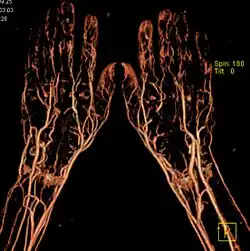

CT-Angiografie der Hände in einer 3D-Rekonstruktion

• Angiographie (Darstellung der Gefäße allgemein)

• Arteriographie (Arterien)

• Phlebographie/Venographie (Venen)